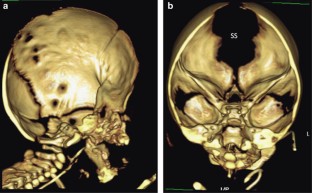

Herman, T., Siegel, M. Apert syndrome with omphalocele. J Perinatol 30, 695–697 (2010). https://doi.org/10.1038/jp.2010.72